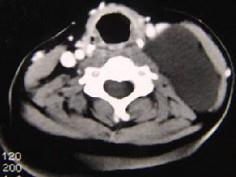

问题 男性,40岁,颈部出现无痛性囊性包块2年余,CT扫描如图所示,最可能诊断为()

选项 A.淋巴管瘤 B.血管瘤 C.淋巴结肿大 D.神经源性肿瘤 E.颈动脉鞘瘤

答案 A